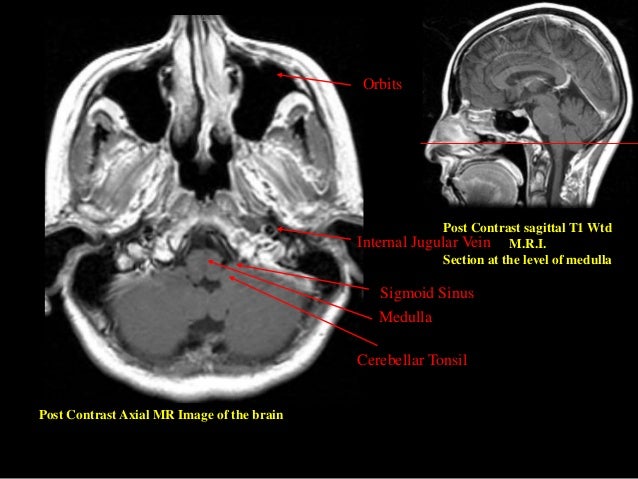

pictures of sinus surgery and disorders otolaryngology houston. Figure 2 ct scan thru the face at he level of the maxillary and ethmoid sinuses. Note how the ethmoids are simply a honeycomb like shape of small sinuses. Maxillary sinusitis and mri treato. 11 of posts and discussions on mri for maxillary sinusitis. Does mri help with maxillary sinusitis? Can mri diagnose maxillary sinusitis ? What are the sinuses? Pictures of nasal cavities. Also strive. The radiology of the maxillary sinus. Imaging of maxillary sinusitis. Waters view of the sinuses, airfluid degree. Ct test of the sinuses. Mri test, coronal and axial views. The opacified paranasal sinus technique and differential. Sinonasal inflammatory ailment with sinus ostial obstruction is a very not unusual cause of an opacified paranasal sinus. But, there may be a differential for an. Mri showed 'mucosal thickening in maxillary sinuses' after. Mri showed 'mucosal thickening in maxillary sinuses' after concussion, what does this mean?